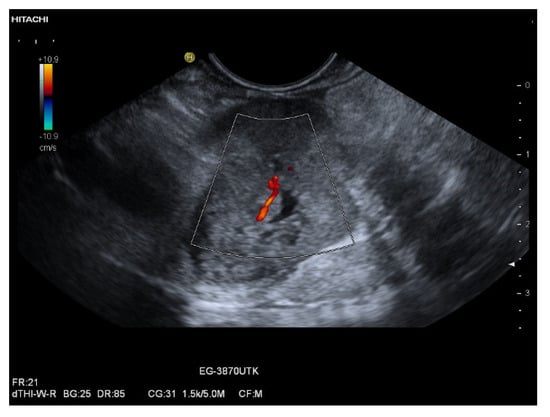

3.3. US and EUS

3.4. CEUS and CH-EUS

| Colour Doppler Imaging | RCC metastases are hypervascularized Most other pancreatic metastases are hypovascularized | No hypervascularization | Hypervascularized |